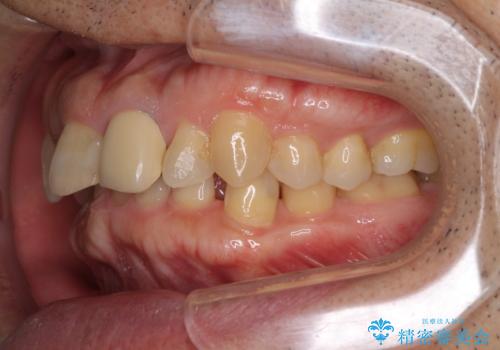

下顎は左右1本ずつ小臼歯が欠損しており、右側にはやや大きな欠損がありました。

欠損により下顎歯列は相対的に小さく、上顎に深く咬みこんでしまうディープバイトとなっていました。

インビザラインによる治療を希望されたため、左側のスペースは閉じ、右側はスペースをより拡大し、インプラント補綴を行うこととしました。